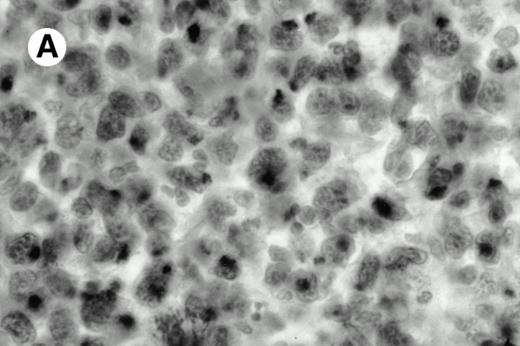

Three cases (cases no. 1 to 3) were located in the nasal cavity. The neoplastic infiltrate consisted of medium and/or large pleomorphic lymphoid cells (Fig 1)intermingled with variable numbers of small lymphoid cells, plasma cells, eosinophils, and histiocytes. Features of angiocentrism and angioinvasion, epitheliotropism, and areas of necrosis were observed in all three cases. Patient no. 4 presented with disease restricted to the lung and an open-lung biopsy was available. The neoplastic infiltrate was composed of large atypical lymphoid cells and was predominantly interstitial without extensive destruction of the normal architecture. Features of angiocentrism, angioinvasion, and epitheliotropism were present (Fig 2A and B). Case no. 5 involved the larynx, extending to the piriform sinus, the ventricle, and the arytenoid. One month later, the lymphoma disseminated to the subcutaneous tissue in the spinal region and biopsy specimens from both sites were available. The neoplastic cells were medium and large, with abundant clear cytoplasm and slightly irregular nuclei with dense chromatin. Epitheliotropism was present in the larynx mucosa. Small foci of necrosis and angiocentrism were seen without angioinvasion. Three patients presented with cutaneous disease. Cases no. 6 and 7 were comparable, as both histories started with necrotic subcutaneous nodules of the thigh, which on histologic analysis were characteristic of cytophagic histiocytic panniculitis without evidence of lymphoma (Fig 3A). Second excisional biopsies of cutaneous nodules obtained 7 and 5 months later, respectively, showed characteristic features of lymphoma in both cases (Fig 3B). However, in case no. 6, skin biopsy specimens showed an epidermotropic PML lymphoma extending to the dermis and the subcutaneous tissue, whereas in case no. 7, the neoplastic infiltrate consisted of a PSC confined to the subcutaneous tissue, admixed with benign histiocytes that showed phagocytosis. Patient no. 8 presented with recurrent skin lesions with spontaneous remission over a period of 10 years. The initial skin biopsies demonstrated an intense epidermotropic neoplastic infiltrate that extended to the superficial and deep dermis composed of atypical PML cells. All cutaneous cases displayed features of angiocentrism, but angioinvasion was observed only in case no. 6 and foci of necrosis in cases no. 6 and 8.

All cases were studied for cytotoxic markers. All of them demonstrated a strong granular cytoplasmic positivity for the cytotoxic granule-associated protein TIA-1. A variable proportion of neoplastic cells were also found positive with Granzyme B (Fig 4A and B) in all cases. Staining for perforin was performed on frozen sections in nine cases, of which seven were positive, one was negative, and the remaining was not interpretable.

Granzyme B expression. (A) Strong paranuclear staining of neoplastic cells in a nasal lymphoma (case no. 3); (B) strong cytoplasmic staining of a few neoplastic cells surrounding intestinal glands in an enteropathy-associated γδ T-cell lymphoma (case no. 11). (Paraffin-embedded section, APAAP technique.)

Granzyme B expression. (A) Strong paranuclear staining of neoplastic cells in a nasal lymphoma (case no. 3); (B) strong cytoplasmic staining of a few neoplastic cells surrounding intestinal glands in an enteropathy-associated γδ T-cell lymphoma (case no. 11). (Paraffin-embedded section, APAAP technique.)